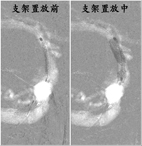

此時右半邊大腦處於嚴重缺血的狀態,若無法即時將血管打通,將會有大範圍中風的情況產生,過去的文獻報導這類的患者死亡率可以高達51%,在集合本院小兒神經科專家與腦中風中心神經放射線科專家共同會診評估後,建議積極使用血管內介入性治療,打通腦部阻塞的血管。醫療團隊將一條微細的導管穿過狹窄的內頸動脈,深入患者右側中大腦動脈,在6小時的黃金時間內,成功將中大腦動脈的血栓溶解,並將原先內頸動脈剝離而狹窄的血管,利用囊球擴張與支架置放,重建血管使其恢復原有的管徑大小,患者出院時除了手部細微動作受到影響外,看不出身體活動有中風過的症狀,目前追蹤已將近一年,無中風再發的情形。

顱內血管支架置放圖,右邊圖用3*12mm囊球擴張支架,剝離的血管再度消失